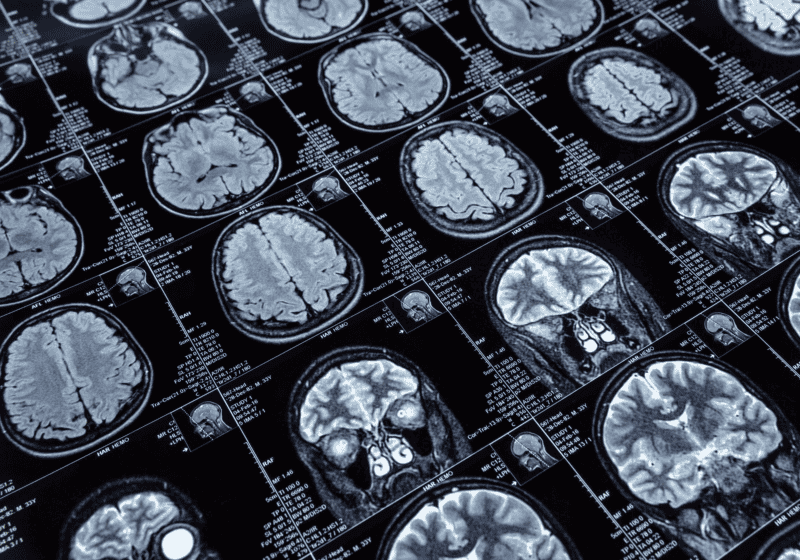

Las inyecciones de las resonancias magnéticas podrían implicar un peligro mortal

El equipo de investigación observó que, incluso en pacientes sin síntomas, las nanopartículas han sido encontradas en tejidos cerebrales y renales, lo que plantea nuevas inquietudes

Un reciente trabajo realizado por especialistas de la Universidad de Nuevo México ha revelado preocupaciones sobre el uso del gadolinio, un metal utilizado como agente de contraste en estudios por resonancia magnética. Según los hallazgos, esta sustancia podría tener consecuencias severas para la salud de ciertos pacientes al interactuar con compuestos presentes en la alimentación.

El gadolinio, un elemento tóxico clasificado dentro de las tierras raras, es ampliamente empleado para mejorar la calidad de las imágenes obtenidas por resonancia magnética. Aunque se considera seguro para la mayoría de los pacientes, el nuevo estudio plantea que, al combinarse con el ácido oxálico (presente en alimentos como espinacas, tomates, frutos secos y algunas frutas), se pueden formar diminutas partículas metálicas que se acumulan en órganos humanos.

La investigación fue publicada en la revista Magnetic Resonance Imaging y analizó cómo estas nanopartículas podrían estar vinculadas a problemas graves en órganos como los riñones y el cerebro. Los expertos también observaron su presencia en sangre y orina incluso años después del procedimiento, lo que sugiere una permanencia prolongada en el organismo.